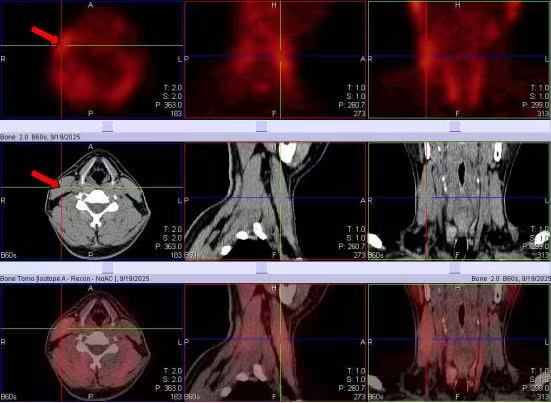

35岁男性,脖子不自主向左倾斜1月余。SPECT前位像示右侧颈部、后位像示双侧颈部多处肌肉的显像剂摄取明显增高(白箭头)。